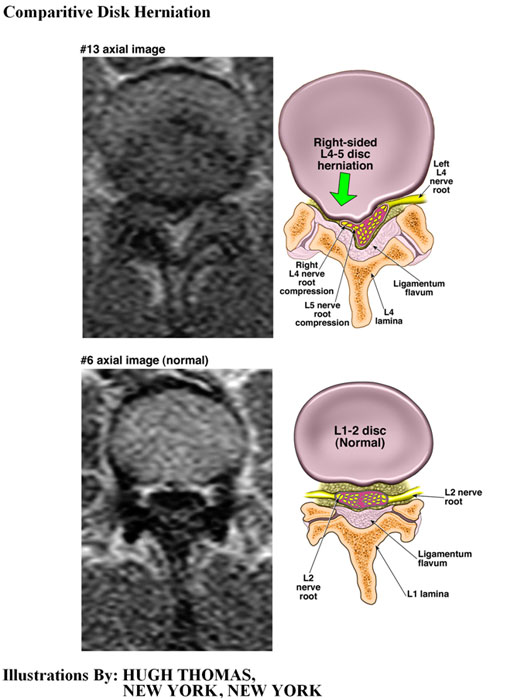

The medical illustrations on this page are examples of the details the attorneys at the Law Offices of William Cafaro prepare for jury presentations.